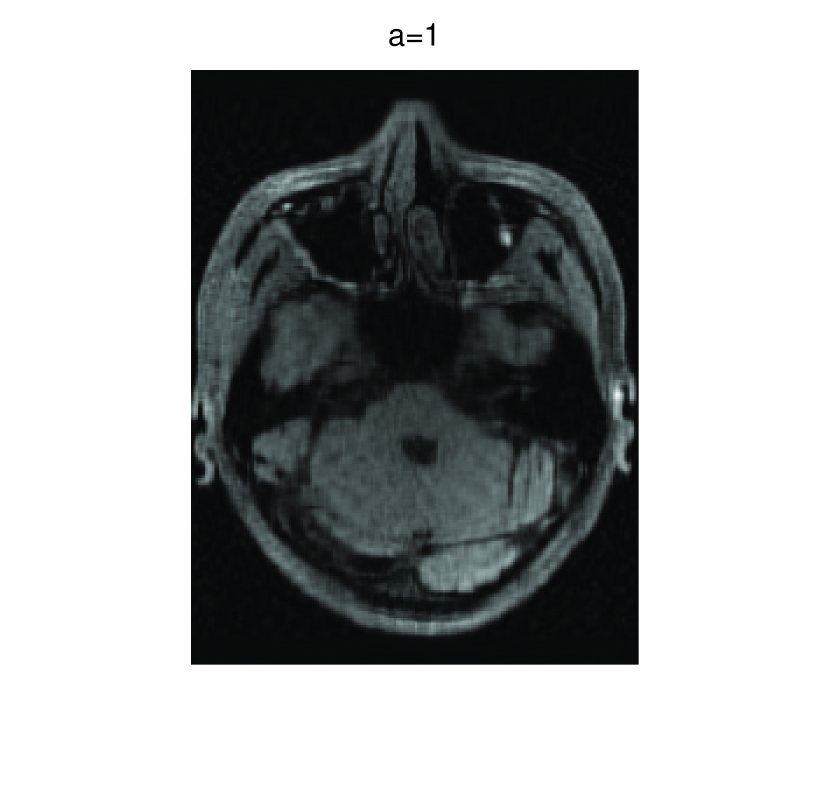

In this subsection, we demonstrate performances of ISVTA on image inpainting problems. The ISVTA is tested on some medical grace images ( Brain angiography image (BAI), Hand angiography image (HAI) and Intracranial venous image (IVI)). We use the SVD to obtain their approximated low-rank images with rank , respectively. Numerical results of ISVTA for theses low-rank image inpainting problems are reported in Table 5, 6, 7, 8.

Table 5, 6 show that ISVTA performs powerful in finding a low-rank matrix on image inpainting problems. Indeed, we could get an exact low-rank image by the ISVTA by choosing proper . Moreover, it is necessary to point out that our method does not work well for all , and we can find that is not a good strategy for the low-rank IVI either or . The numerical results of ISVT, SVTA and SVPA compared in Table 5, 6, 7, 8, 9, 10 under same circumstance show that the ISVT algorithm performs far more better than ISTA and SVPA on image inpainting problems for some proper .